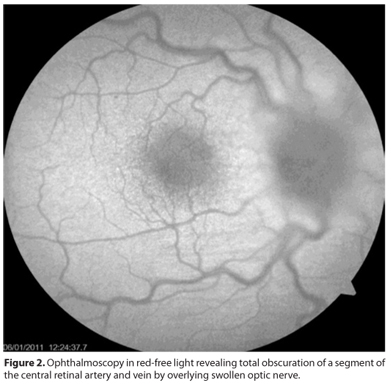

Systemic workup included: complete blood counting with differential classification, rheumatoid factor, antinuclear antibody, sedimentation rate, human immunodeficiency virus test, venereal disease research laboratory test, anticardiolipin antibody, chest and sacroiliac radiographies and Toxoplasma gondii and cytomegalovirus serologies. As anterior uveitis was diagnosed, the patient began treatment using 1% prednisolone eye drop 4 times a day and 1% atropine sulfate, b.i.d. , while we waited for the exam results. One week later, laboratory investigation failed to find a systemic disease and the patient got worse, with visual acuity of counting fingers at 1 meter in OD. The ACR of OD revealed 1+ cell, and fundus examination revealed diffuse optic disc swelling with no hemorrhages or abnormal vasculature, with no macular abnormalities (Figures 1 and 2). Cranial magnetic resonance imaging was performed and a sample of the cerebrospinal fluid was obtained. Both exams revealed no abnormalities, except from thickening of the right sphenoid sinus.